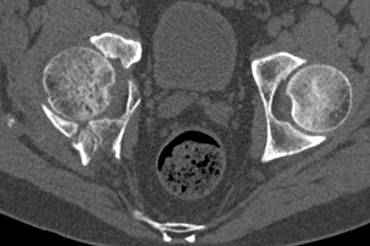

высылаю дополнительно сканы.

По отдельным срезам и тем более по реконструкции трудно судить о сращении крыла и задней колонны с осевым скелетом.

В большинстве случаев при двухколонных переломах

в итоге получается прочный бублик с дыркой. При эндопротезировании в дырку помещается головка, а чашка должна неплохо заклиниться в бублике.

Главное, чтобы бублик не был разорван, что не очень понятно на представленных снимках.

Хорошо бы на рентгенограммы взглянуть и побольше срезов по своду. С каким отломком головка контактирует и как ее состояние.

Из того минимума, что представлено, мне кажется, мы имеем дело с двухколонным переломом вертлужной впадины. Обычно медиальный (центральный) "вывих" головки встречаются в сложных двухколонных переломах со смещением.